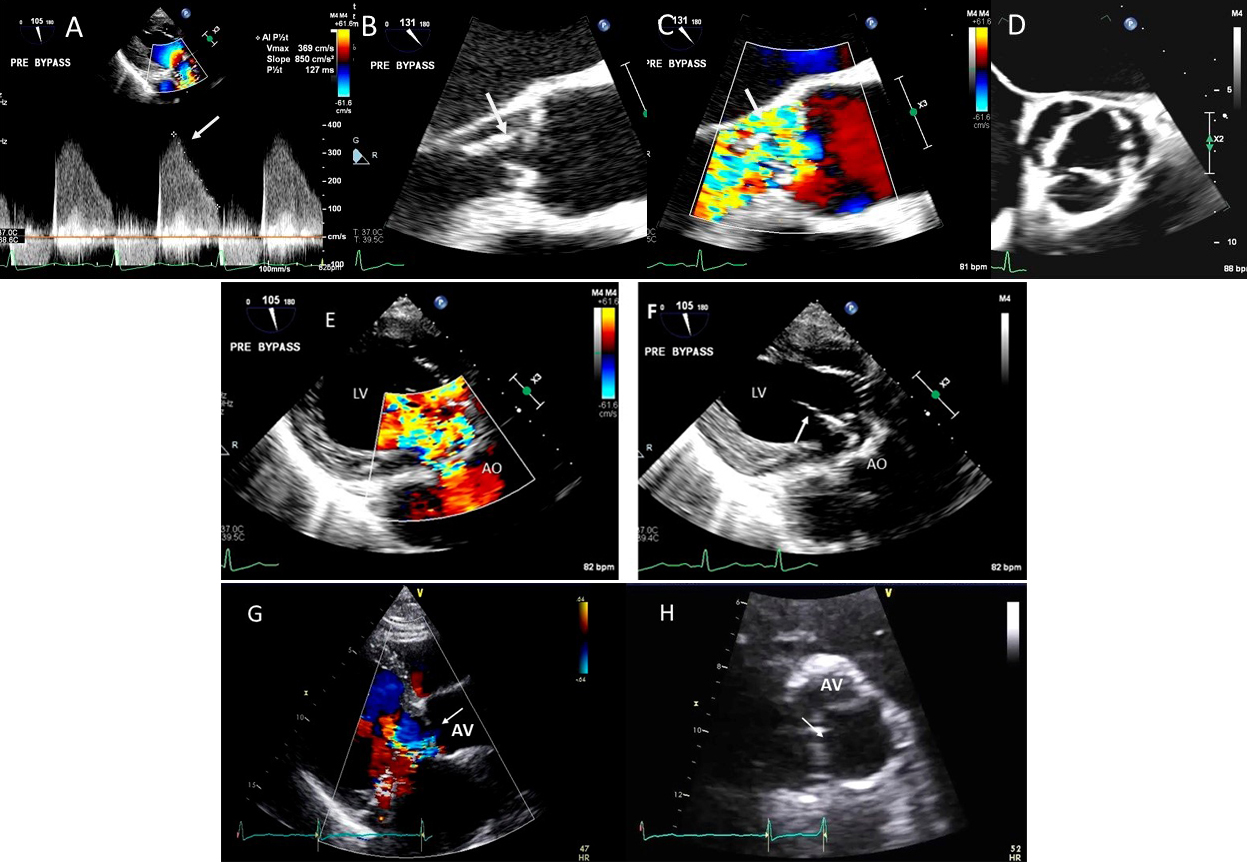

Fig. 8.Aortic regurgitation and left coronary cusp perforation. (A) TTE color Doppler parasternal short axis view demonstrating left coronary cusp perforation (white arrows), resulting in aortic regurgitation. (B) TTE color Doppler short axis view showing origin of aortic regurgitation through the left coronary cusp perforation (white arrow). (C) TEE color Doppler short axis view showing a better delineation of the origin of aortic regurgitation jet through the left coronary cusp perforation (white arrow). (D) TEE long axis view demonstrating the perforated coronary cusp on 2D (white arrow) with aortic regurgitation jet originating through the perforation (white arrow) and not through the aortic leaflet coaptation. (E) 3-dimensional (3D) TEE short axis view of the aortic valve showed a clear definition of the left coronary cusp perforation (white arrow). (F) 3-D TEE color Doppler short axis view showing aortic regurgitation jet originating through the left coronary cusp (black arrowhead). Direct planimetry of color Doppler aortic regurgitant orifice can be performed online or via offline post processing of 3D data sets without geometrical assumptions of PISA method or continuity equation.

Fig. 9.Aortic valve regurgitation induced by dilated annulus. (A)

Transthoracic echocardiogram parasternal long axis view showing

markedly dilated aortic sinuses (red arrow). (B) Imaging at a higher parasternal window shows aneurysmal aortic sinuses (red arrow)

and normal ascending aorta above sinotubular junction.

(C) Three chamber view with continuous-wave (CW) Doppler showing dense AI Doppler

envelope with a steep deceleration slope (red arrows) suggesting severe AI. (D) CW Doppler recording at the proximal descending thoracic aorta

demonstrating pandiastolic flow reversal (red arrows), another feature of severe AI.

(E) Color Doppler parasternal long axis view showing AI color

jet occupying two third of the LV outflow tract with a wide vena contracta at origin from the aortic valve leaflets (